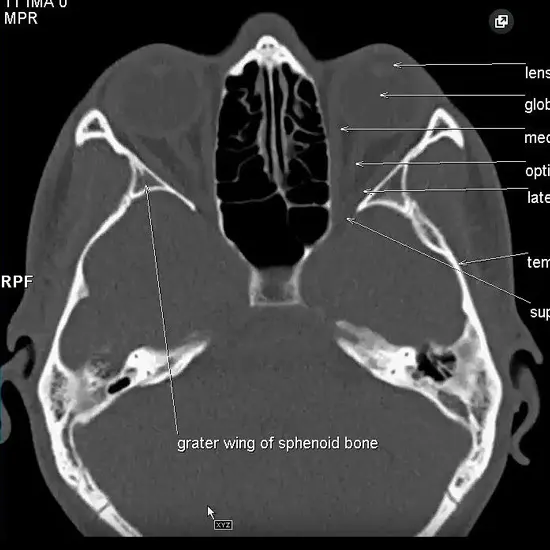

NCCT PNS CORONAL is a Non-Contrast Computed Tomography scan of the Paranasal Sinuses Coronal view. It is an imaging procedure that obtains images of the Paranasal Sinuses from front to back. This scan helps assess and diagnose the suspected diseases of the sinuses.